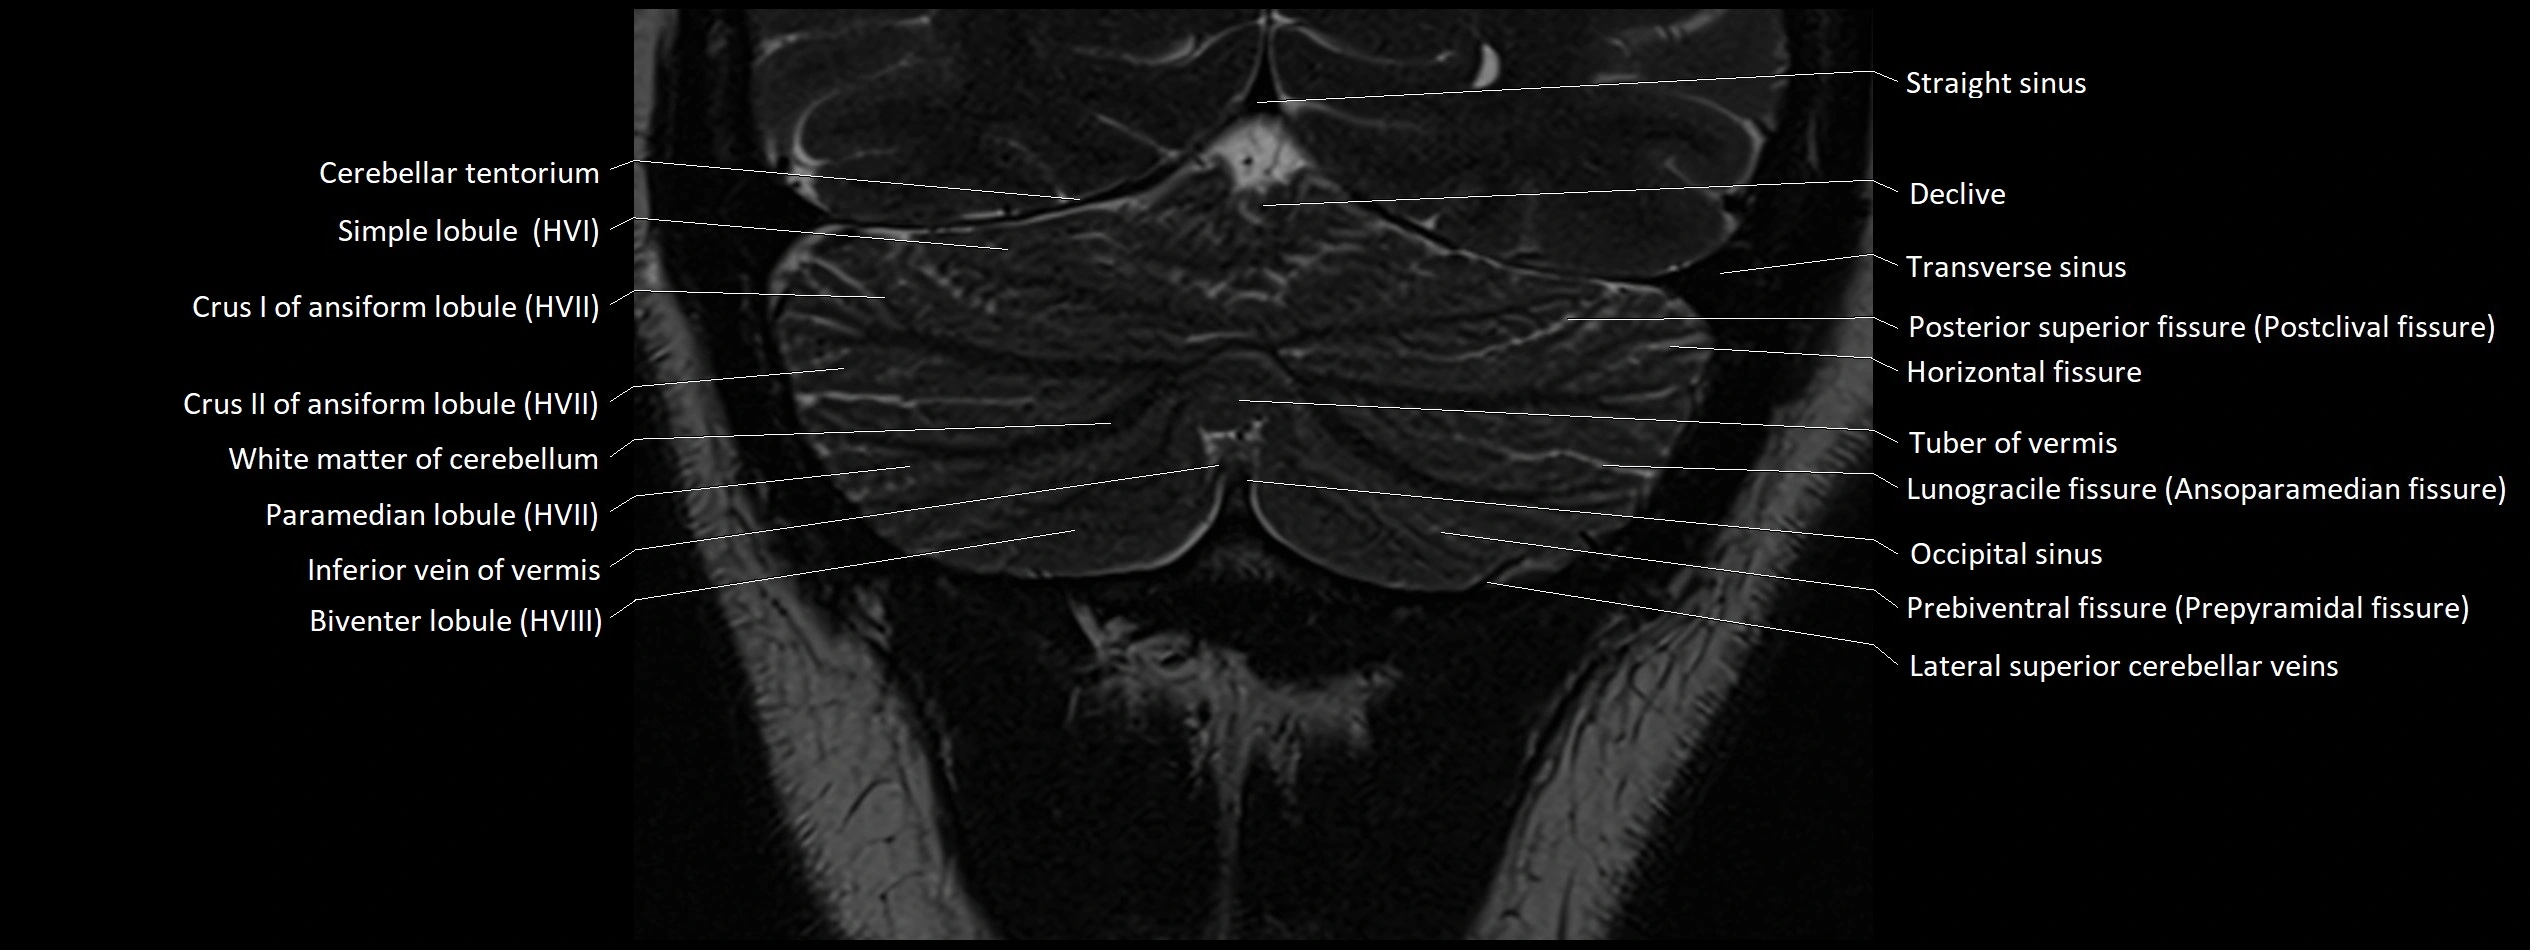

- Biventral lobule (HVIII) of cerebellum

- Cerebellar tentorium

- Crus I of ansiform lobule of cerebellum

- Crus II of ansiform lobule of cerebellum

- Declive

- Horizontal fissure (cerebellum)

- Inferior cerebellar veins

- Inferior hemispheric veins of the cerebellum

- Inferior vein of vermis

- Lunogracle fissure

- Lunogranicile fissure of cerebellum

- Occipital sinus

- Paramedian lobule

- Paramedian lobule (HVII) of cerebellum

- Posterior superior fissure

- Prebiventral fissure

- Simple lobule

- Simple lobule (HVI) of cerebellum

- Straight sinus

- Superior cerebellar vein

- Superior hemispheric cerebellar veins

- Superior hemispheric veins of the cerebellum

- Transverse sinus

- Tuber of vermis

- Tuber of vermis (VII)